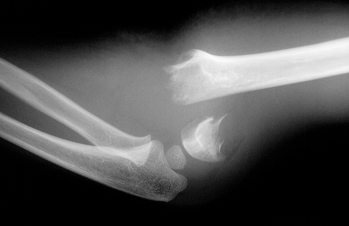

- Fractures : je vous ai mis en image une fracture très fréquente causée par une chute de trampoline, au niveau du bras. Ce type de fracture est grave et nécessite souvent une opération en urgence avec pose de broches;